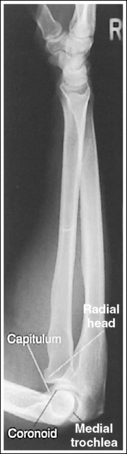

External AP oblique projection: The capitulum-radial joint is open, and the radial head articulating surface is not demonstrated.

Internal AP oblique projection: The trochlea-coronoid process joint is open, and the coronoid process articulating surface is not demonstrated.

The elbow has been internally rotated 45 degrees. The coronoid process, the trochlear notch, and the medial aspect of the trochlea are demonstrated in profile. The trochlear-coronoid process articulation is open, and the radial head and neck are superimposed over the ulna.

• An accurately positioned internally rotated AP oblique elbow projection is obtained by placing the arm in an AP elbow projection and then internally rotating the hand and humerus until the humeral epicondyles are at a 45-degree angle to the IR (Figure 4-74). When the elbow obliquity is correct, the coronoid process is demonstrated in profile and the radial head and tuberosity are superimposed over the ulna. If the humeral epicondyles are at less than 45 degrees of obliquity, the radial head is demonstrated lateral to the coronoid process and does not entirely superimpose the ulna (see Image 83). If the humeral epicondyles are at more than 45 degrees of obliquity, the radial head is partially visualized anterior to the coronoid process (see Image 84).

The elbow has been externally rotated 45 degrees. The capitulum and radial tuberosity are demonstrated in profile, the radial head, neck, and tuberosity are visualized without superimposing the ulna, and the radioulnar articulation is demonstrated.

• Accurate positioning for an externally rotated AP oblique elbow projection is achieved by positioning the arm in an AP projection and then externally rotating the humerus and forearm until the humeral epicondyles form a 45-degree angle with the IR (Figure 4-75). This positioning rotates the radius away from the ulna, demonstrating it without superimposition. If the humeral epicondyles are at less than 45 degrees of obliquity, the radial head and tuberosity still partially superimpose the ulna (see Image 85). If the humeral epicondyles are at more than 45 degrees of obliquity, the coronoid process is partially superimposed over the radial head, and the radial neck and tuberosity are free of superimposition; the radial tuberosity is no longer in profile (see Image 86).